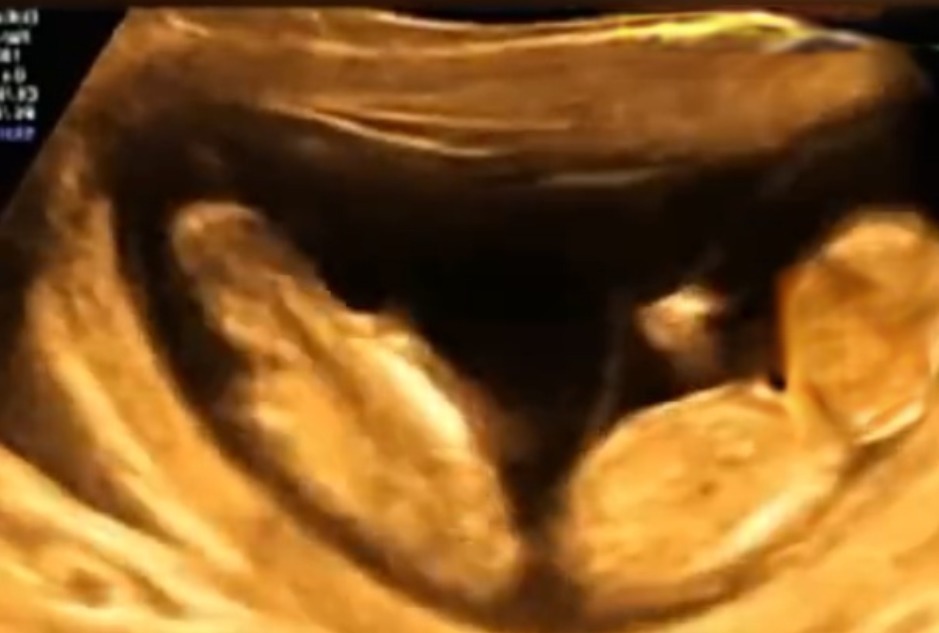

可能孩子在妈妈肚子里在汲取营养或是吮吸手指,这是常见的现象。但生活中也有十分罕见的,在河南有一位孕妈做四维彩超的时候突然开始腹痛,能感受到宝宝在肚子里的活动。做B超的时候发现两个宝宝正在闹着玩,在妈妈的肚子里打架。看到了这两个宝宝的未来一定是一个挨揍一个受欺负。网友们纷纷震惊评论说“看起来是单方面的在挨打。”“所以我下个月预产期,等他长大了我就找机会揍他一顿,不然不能泄愤。”“抢位置大作战。”